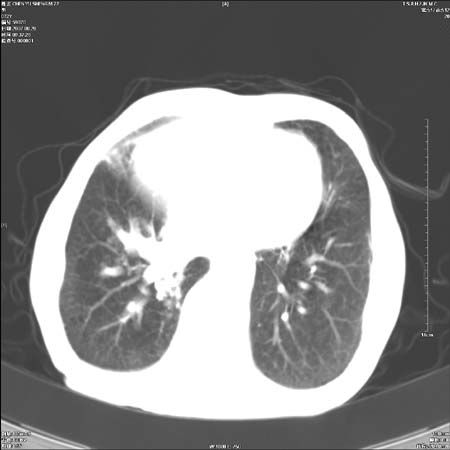

男性,72岁,既往肺结核,今复查。无前片对比。

右侧中央型肺癌伴中叶不张可能性大,建议增强扫描.右上肺陈旧性肺结核.慢性支气管炎伴肺气肿.右侧少量胸腔积液.

中心性肺癌肺转移

右侧中央型肺癌伴中叶不张可能性大,建议纤支镜检查.右上肺陈旧性肺结核.肺气肿。

典型右肺中心型肺癌

右侧中央型肺癌伴肺不张可能性大,建议增强扫描.右上肺陈旧性肺结核.慢性支气管炎伴肺气肿.右侧少量胸腔积液.

右肺中心型肺癌

右侧中央型肺癌.上肺陈旧性肺结核.

1右侧中央型肺癌伴中叶不张2右侧少量胸腔积液3右上肺陈旧性肺结核

1.右肺中心性肺癌并右肺中叶综合征2。右侧胸腔少量积液3。右肺上叶结核球已钙化,4。慢支伴肺气肿

右侧中央型肺癌伴中叶不张可能性大,建议纤支镜检查.右上肺陈旧性肺结核.肺气肿。

右侧中央型肺癌伴中叶不张可能性大,建议增强扫描.右上肺陈旧性肺结核.慢性支气管炎伴肺气肿.右侧少量胸腔积液.

右侧中央型肺癌伴中叶不张

右肺中央型肺癌伴右肺中叶不张。

右上肺陈旧性肺结核。

支持右肺中心型肺癌并中叶不张,右上肺陈旧性肺结核钙化,右侧少量胸腔积液。

支持右侧中央型肺癌伴中叶不张可能性大,建议增强扫描.右上肺陈旧性肺结核.慢性支气管炎伴肺气肿.右侧少量胸腔积液.

右侧中心型肺癌可能性大.肺气肿.胸腔积液.

支持 1右侧中心型肺癌伴中叶不张2右侧少量胸腔积液3右上肺陈旧性肺结核4双肺局限性肺气肿

1,右侧中央型肺癌.

2,右上肺陈旧性肺结核.

1.右侧中央型肺癌伴中叶不张,建议纤支镜检查.

2.右上肺陈旧性肺结核.

3.肺气肿。

4.右侧少量胸腔积液.

右侧中央型肺癌伴中叶不张并纵隔淋巴结增大,建议增强扫描.右上肺陈旧性肺结核.慢性支气管炎伴肺气肿.右侧少量胸腔积液。

右肺中心型肺癌并肺不张,陈旧性肺tb.慢支,肺气肿.

陈旧性肺结核.慢性支气管炎伴肺气肿,中央型肺癌伴中叶不张。

右侧中央型肺癌伴中叶不张可能性大;右上肺陈旧性肺结核.慢性支气管炎伴肺气肿

陈旧性结核是存在,但真正致命的却是右侧中心型肺癌。